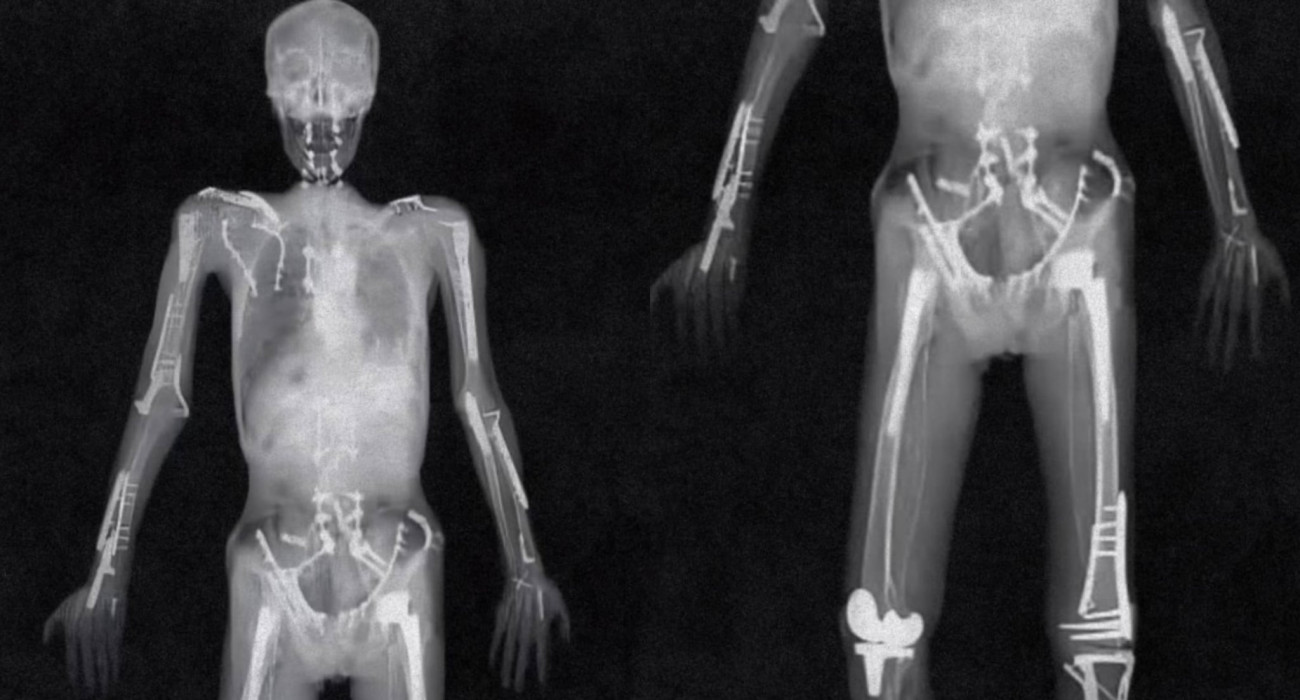

Αυτή είναι η θρυλική ακτινογραφία του Τράβις Παστράνα

Στην εποχή του AI (τεχνητή νοημοσύνη) που δημιουργεί με ακαταμάχητη ταχύτητα ψευδείς εικόνες (κινούμενες ή στατικές), μέχρι και οι γιατροί που αντίκρισαν την ολόσωμη ακτινογραφία του Τράβις Παστράνα ήταν επιφυλακτικοί. Με μία γρήγορη ματιά αδυνατούσαν να πιστέψουν ότι το σώμα ενός αθλητή είναι δυνατόν να έχει... κακοποιηθεί τόσο έντονα από τραυματισμούς. Με μία πιο ψύχραιμη και αναλυτική προσέγγιση όμως, κατάλαβαν την αλήθεια που οπτικοποιούσαν τα X-Ray.

Για χρόνια ο Παστράνα έσπαγε τα κόκκαλά του με υπερβολικά μεγάλη συχνότητα. Στην θρυλική ακτινογραφία του που «κυκλοφορεί» στο διαδίκτυο, αλλά και στα ιατρικά γραφεία σαν ένα είδους μοναδικής περίπτωσης, είναι τρομακτικοί. Κακώσεις, μοσχεύματα, λάμες, βίδες. Ότι θα μπορούσε να χρησιμοποιήσει ένας χειρουργός σε ένα σώμα, τα έχει το δικό του.